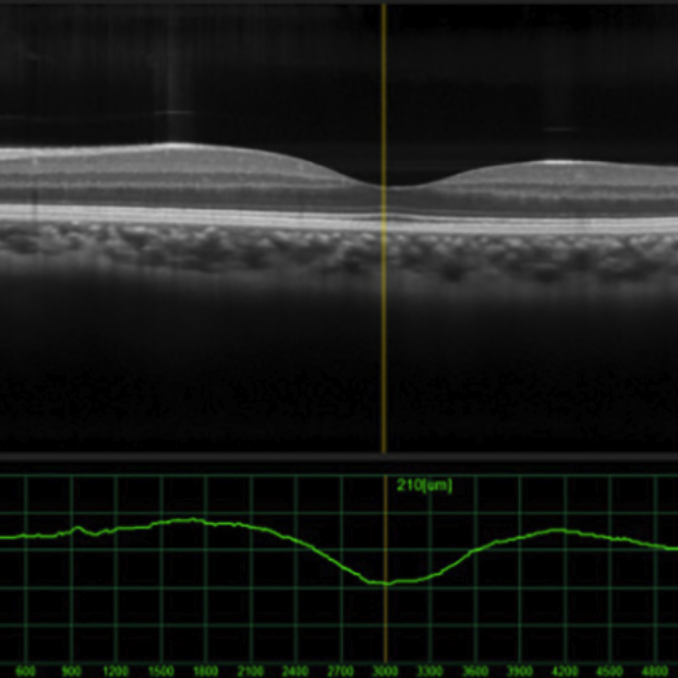

Fundamentals of OCT

$150 | Self-Paced |  6 credits

Instructors:

George Asimellis, PhD, MBA

Elena Biffi, OD, MSc, FAAO

Timothy Bossie, OD, FAAO

Joseph Kane, OD, FAAO

Jennifer Reilly, OD, MS, FAAO

OCT has become a gold standard in the delivery of eye care to diagnose and manage posterior segment diseases of the optic nerve and retina, in particular, glaucoma and macular diseases. This six-part course provides a continual curriculum of OCT technologies, from basic physical science concepts to image interpretation, analysis, and management of pathology.